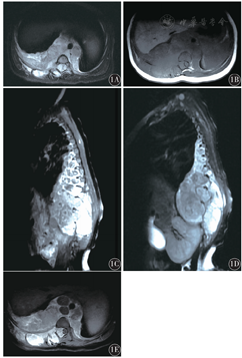

平扫T1WI呈等信号12例,低信号4例;平扫T2WI呈均匀高信号9例,混杂高信号7例;肿瘤内部伴出血坏死囊变钙化11例;增强扫描的12例患儿中,呈轻度强化2例,中度强化5例,明显强化5例(图1)。

14例手术患者中肿瘤有完整包膜9例,包膜不完整或无包膜5例,其中肿瘤侵犯周围脏器2例;16例中,肿瘤其他部位转移7例,其中转移到骨骼5例,骨髓2例,淋巴结2例,左肺1例,骨及软组织多发1例。肿瘤切面呈灰白4例,灰褐6例,灰白灰褐4例;肿瘤内出血2例,钙化2例,坏死3例,囊变1例,出血坏死2例,坏死钙化2例,出血钙化2例。肿瘤合并胸腔积液4例,肺炎4例,Horner综合征4例,肺实变或肺不张1例。